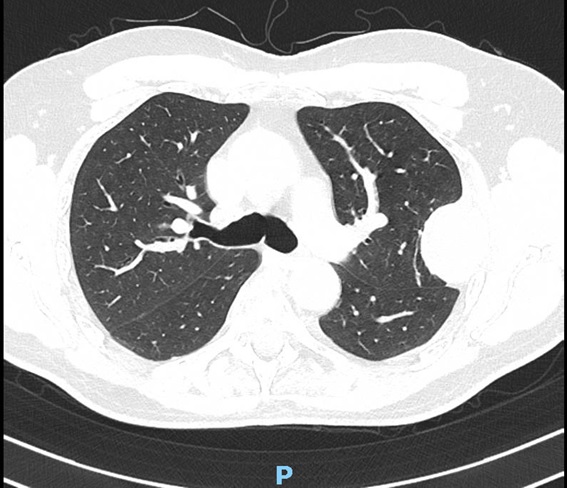

A su llegada a urgencias se realiza analítica complementa y una tomografía computerizada dorsolumbar objetivandose metástasis óseas cervical, dorsal D4, D6, D12 y afectación cuarto arco costal, se decide ingreso para estudio diagnosticándose un mieloma múltiple.

Se realiza radiografía de lumbar, dorsal y destaca chafamiento de D4 y una disminución radiodensidad ósea en todos los cuerpos vertebrales.